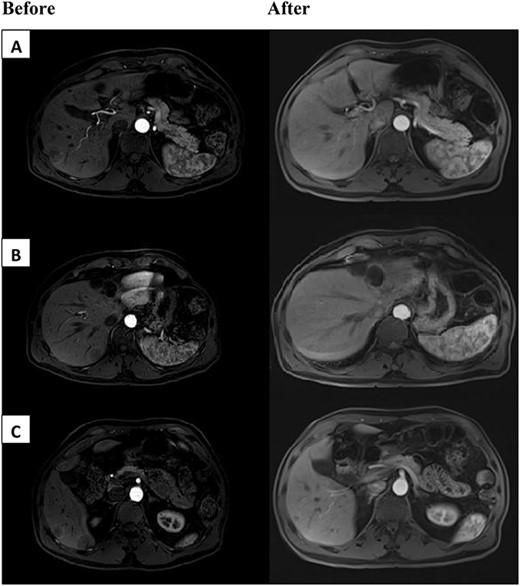

We encountered a 67-year-old gentleman who was initially diagnosed with rectal cancer. This was determined to be 3 cm from the dentate line. MRI pelvis demonstrated T3N0 disease. The patient underwent neoadjuvant chemoradiation with capecitabine followed by low anterior resection with diverting loop ileostomy. The final pathology showed ypT3ypN0 disease. The patient deferred adjuvant chemotherapy. He subsequently underwent ileostomy takedown. The patient developed five liver lesions 2–3 cm in size on surveillance imaging 2 years later. He had a subsequent liver biopsy, which confirmed metastatic disease. The tumor was microsatellite stable. The CEA was 0.9 ng/ml at the time. The patient then underwent chemotherapy with FOLFOX and bevacizumab for 2 months. Unfortunately, he developed pancytopenia, poor appetite and functional decline on therapy. He was not felt to be a surgical candidate at this time. Additional testing on the tumor noted it to be Kirsten rat sarcoma virus (KRAS) wild-type (WT) and B-raf gene (BRAF) WT. The tumor was also noted to be 3+ for HER2 expression on immunohistochemistry (IHC). Given the decline in performance status and progression of the disease, he was then switched to dual Her2 antagonists, trastuzumab and pertuzumab therapy. The patient’s performance status improved and he tolerated the treatment without additional complications. The patient was then seen in hepatobiliary surgery clinic 4 months after initiation of trastuzumab and pertuzumab with interval MRI demonstrating marked reduction of metastatic disease (Fig. 1). After discussion in the multidisciplinary tumor board, the patient underwent definitive nonanatomic resection of the five different tumors. Pathology demonstrated ‘benign liver parenchyma with foci of fibrosis and inflammatory reaction consistent with treated metastasis’. This confirmed complete pathologic response in the patient after dual anti-HER2 therapy for metastatic rectal cancer. At the time of recent 1-year follow-up there was no evidence of recurrent disease.

Above are representative images demonstrating severity of patient’s tumor burden, before (left) and after (right) dual anti-HER2 therapy. Patient had bilobar liver metastases ranging from 2.5 to 3 cm in segments 5, 7 and 8. Before images appear different than after due to institutional variation of MRI scanners.